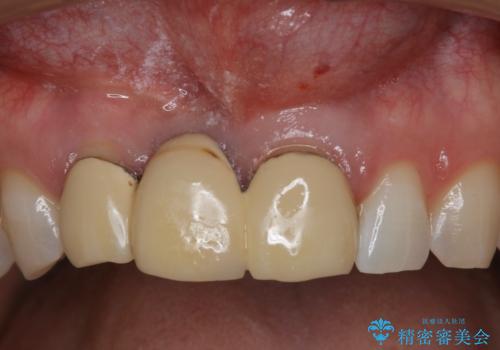

- 前歯ブリッジのやり変えを希望され来院された患者様です。

審美性を重視されていたので、オールセラミッククラウン(スペシャル)でのブリッジを選択されました。